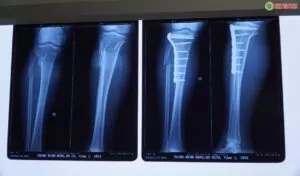

Trong quá trình khám lâm sàng và kiểm tra các xét nghiệm hình ảnh, bệnh nhân được chẩn đoán gãy xương cẳng chân phải, gãy phức tạp 1/3 trên 2 xương cẳng chân. Qua khám sức khỏe tổng quát, khai thác tiền sử bệnh, kết quả cho thấy bệnh nhân có tiền sử bệnh cơ tim do thiếu máu cục bộ. Theo dõi hồ sơ bệnh án, đội ngũ y bác sĩ đã tiến hành hội chẩn và quyết định phẫu thuật kết hợp xương trên màn hình tăng sáng đối với trường hợp của ông H.

trước và sau phẫu thuật

Dưới sự phối hợp chặt chẽ của Bác sĩ CKI Nguyễn Huỳnh Quang Huy và nhiều chuyên khoa, đội ngũ y bác sĩ chuyên môn cao, giàu kinh nghiệm, ca phẫu thuật điều trị gãy xương cẳng chân đã diễn ra thành công, sức khỏe bệnh nhân sau đó cũng được phục hồi nhanh chóng dưới sự quan tâm theo dõi của đội ngũ y tế.